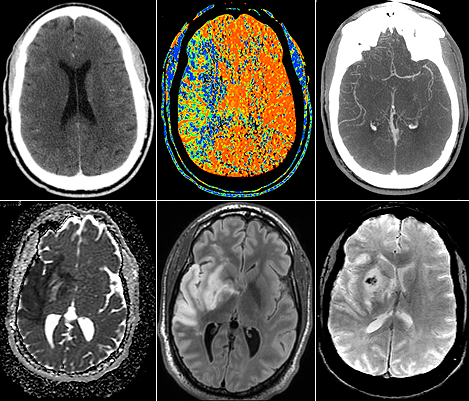

Les neuroradiologues ont une formation en radiologie diagnostique pour étudier diverses maladies telles que les accidents vasculaires cérébraux, les maladies démyélinisantes, les maladies neurodégénératives, les tumeurs cérébrales, les cancers de la tête et du cou, les maladies neurovasculaires, les traumatismes, les douleurs dorsales et d'autres maladies neurologiques.

Les principales modalités d'imagerie sont la tomodensitométrie (Scanner) et l'imagerie par résonance magnétique (IRM).